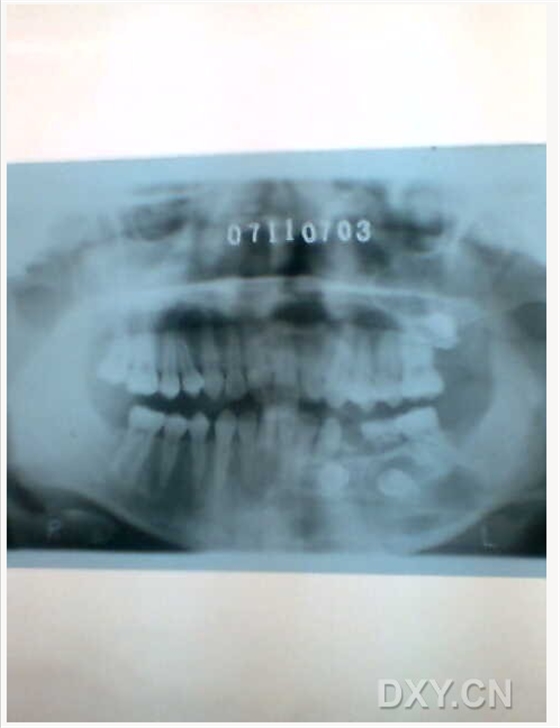

根尖囊腫